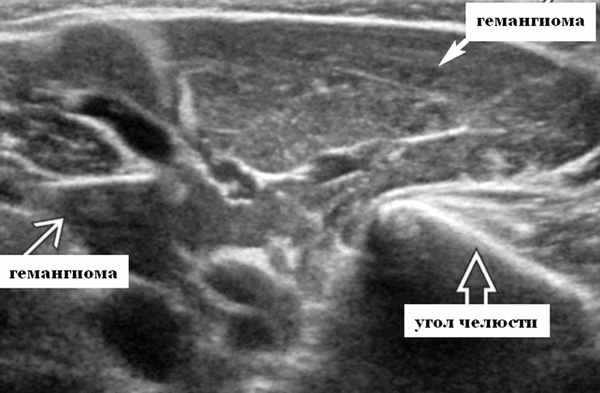

Лучшая диагностическая подсказка. Четко выраженная опухоль с диффузной гиперваскуляризацией внутри очага поражения / интенсивным усилением кровотока на УЗИ с ЦДК. Сосуды внутри и рядом с образованием во время фазы пролиферации (ФП). Уменьшение размера за счет замещения жировой ткани во время фазы инволюции (ФИ)

Результаты ультразвукового исследования слюнных желез

Серошкальное УЗИ. Четко выраженная солидная некальцинированная опухоль мягких тканей. Однородная картина эхоструктуры. ПФ: Гипоэхогенный вид по сравнению с паренхимой околоушной железы; ИФ: эхоструктура от изо- до умеренно гиперэхогенной